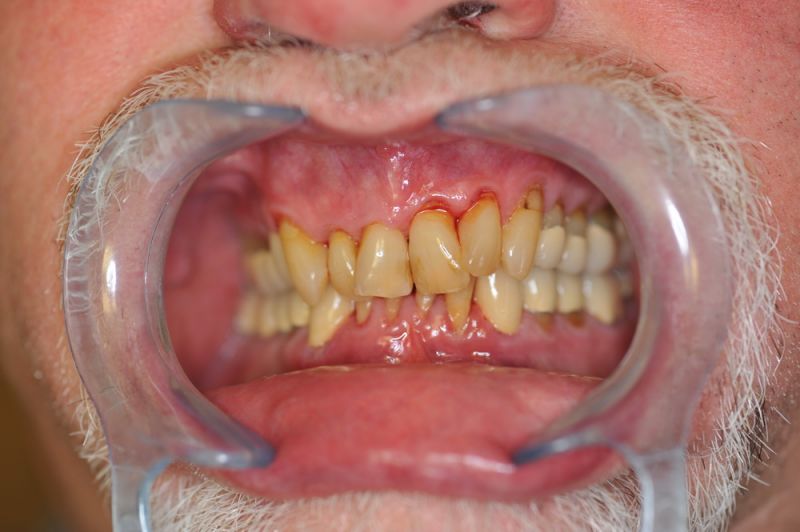

80 jähriger Patient aus Kiel erhält die beiden letzten Rekonstruktionen. Behandlung abgeschlossen

Der Patient erhält die beiden letzten Kronen zur Einstellung der dynamischen Okklusion.

Die funktionstherapeutische Behandlung ist damit abgeschlossen. Der Patient ist vollkommen beschwerdefrei. Beschwerdelevel: "0".

Das Weihnachtsgeschenk des Patienten nach zweieinhalb Jahren zahnärztlicher Funktionsdiagnostik und -therapie.

Trotz der langen Behandlungszeit ist der Patient glücklich, dass er die Behandlung absolviert hat, weil er seit Eingliederung des adjustierten Aufbissbehelfs vollkommen beschwerdefrei ist.